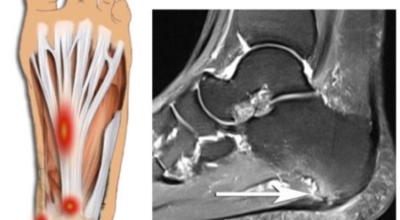

족저 근막이란 발가락 시작지점부터 발뒤꿈치뼈까지 발바닥 전체를 감싸고 있는 두꺼운 막을 말해요. 족저 근막은 발바닥 아치를 보존시켜 발바닥이 지면을 내딛음으로써 생기는 쇼크을 흡수하는 중요시되는 역할을 수행하고 있어요. 이 족저 근막에 일차적으로 서서히 조직 훼손이 일어나고 계속적인 활동에 의하여 염증이 커지면서 발 뒤꿈치 부근 통증을 일으키게 되는데 염증은 무리하고 반복적인 동작, 많은 활용으로 마찰에 의해 발생해요.

족저 근막염은 염증에 의한 훼손 및 통증을 유발하는 질환인데요 족저 근막염 증상은 동일한 발뒤꿈치 통증 하글런드 병변의 기형으로 알려져 있으고 아킬레스 건과 연관이 깊다고 해요. 특히 근육이 덜 풀린 아침 시간 대는 보행 시 날카롭고 바늘로 찌르는 듯한 심한 통증을 느끼게 된다고 해요. 하지만 아침 시간 대를 지나 오후에 접어들면서 일정 양 통증은 서서히 감소하기 시작한다고 하는데요 초기 증상이 나타난다면 필수로 전문의를 찾아 조기치료하는 것이 바람직해요.

비수술적 치료 방법에으로 보조기, 체외쇼크파, 스트레칭, 스테로이드 주사요법, 비스테로이드성 소염진통제 등이 여러 방법들이 있어요. 족저근막염 발생초기에는 스트레칭을해서 족저근막 및 아킬레스건을 효과적으로 증가시키는 것만으로 추가적인 피해를 예방할 수 있답니다. 또한 보조기를 착용하여 뒤꿈치에 가해지는 쇼크을 완화 시킬 수 있답니다. 발에 부기가 발생된 경우 진통주사를 이용해 치료할 수 있어요. 수술적 치료로 들어가기 전 체외쇼크파를 이용해 증상완화의 효과를 볼 수 있다고 하죠.